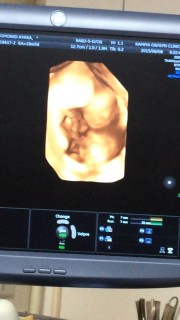

4週間ぶりのエコー検査、顔がはっきり見えてびっくり!どことなく旦那にのような。性別判定はまだだと思っていたのに男の子と判明しました!